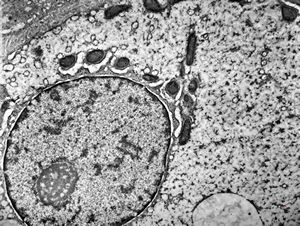

M,19y. | normal hepatocyte